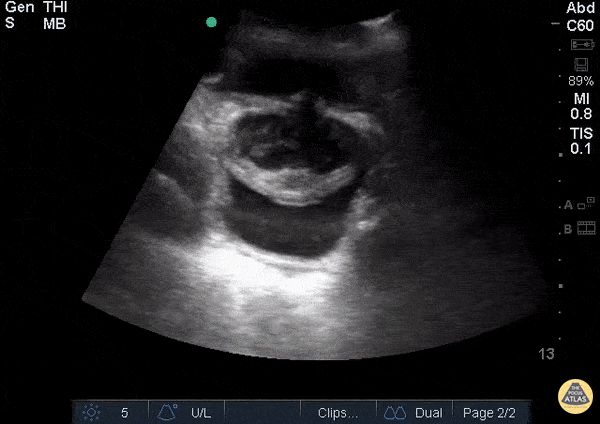

View: Unspecified Parasternal Long Axis Parasternal Short Axis Apical Four-Chamber Subcostal Four-Chamber Subcostal Inferior Vena Cava Right Upper Quadrant Left Upper Quadrant Suprapubic Longitudinal Suprapubic Transverse Subxiphoid Anterior Thoracic Phrenic